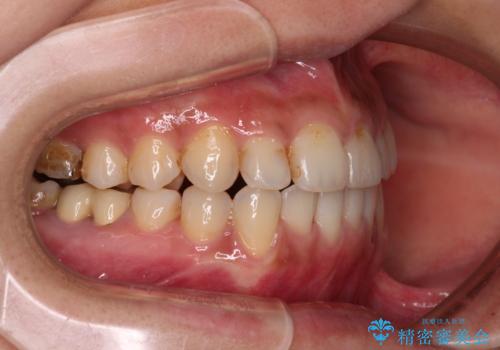

前歯のデコボコとクロスバイト インビザラインによる矯正治療

- 上下のクロスバイトと前歯のデコボコを気にして来院された患者様です。

骨格的に下顎がやや前方にあり、奥歯にクラウンが装着されているため、矯正治療後半の不安定な咬み合わせを避けるのであればワイヤー矯正がおすすめとなりますが、希望によりインビザラインにて治療を行うこととしました。

インビザラインを用い、IPR(歯と歯の間を削る)と歯列全体を拡大させることで、歯並びを整えていくこととしました。

懸念されたとおり、右下のクラウン部分が全く咬み合わず、仕上げの段階で治療期間が長くなりました。